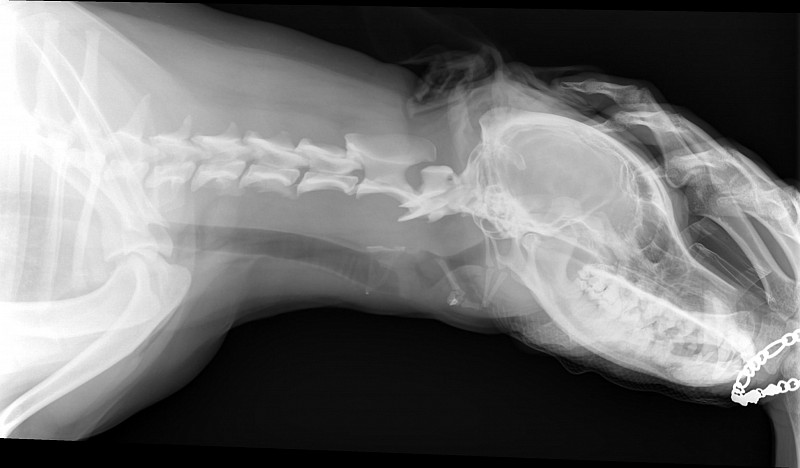

Рентгеновские снимки головы кошки в боковой проекции